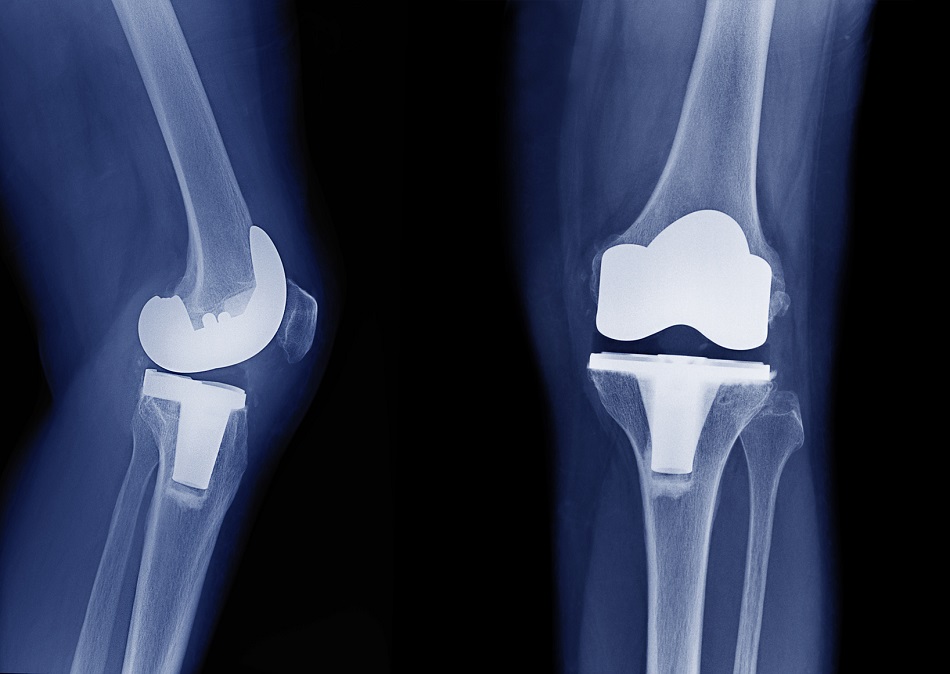

El agregado de dos dosis de dexametasona al tratamiento multimodal del dolor luego de la cirugía de reemplazo de rodilla redujo el dolor y el consumo de morfina durante las primeras 48 horas de posoperatorio. British Medical Journal,  4 de enero de 2022.

Eficacia y seguridad de los fármacos antiinflamatorios no esteroideos (AINE) y opioides para la artrosis de rodilla y cadera

Etoricoxib 60 mg/día y diclofenac 150 mg/día parecen ser los AINE orales más eficaces para el dolor y la función en pacientes con artrosis. Pero, estos tratamientos probablemente no sean apropiados para pacientes con comorbilidades o para uso a largo plazo por un ligero aumento en el riesgo de eventos adversos. Hay un mayor riesgo de abandono debido a eventos adversos con el diclofenac. El diclofenac tópico 70-81 mg/día parece ser eficaz y más seguro y debe considerarse como tratamiento farmacológico de primera línea para la artrosis de rodilla. El balance beneficio/riesgo de los opioides es negativo. BMJ, 12 de octubre de 2021